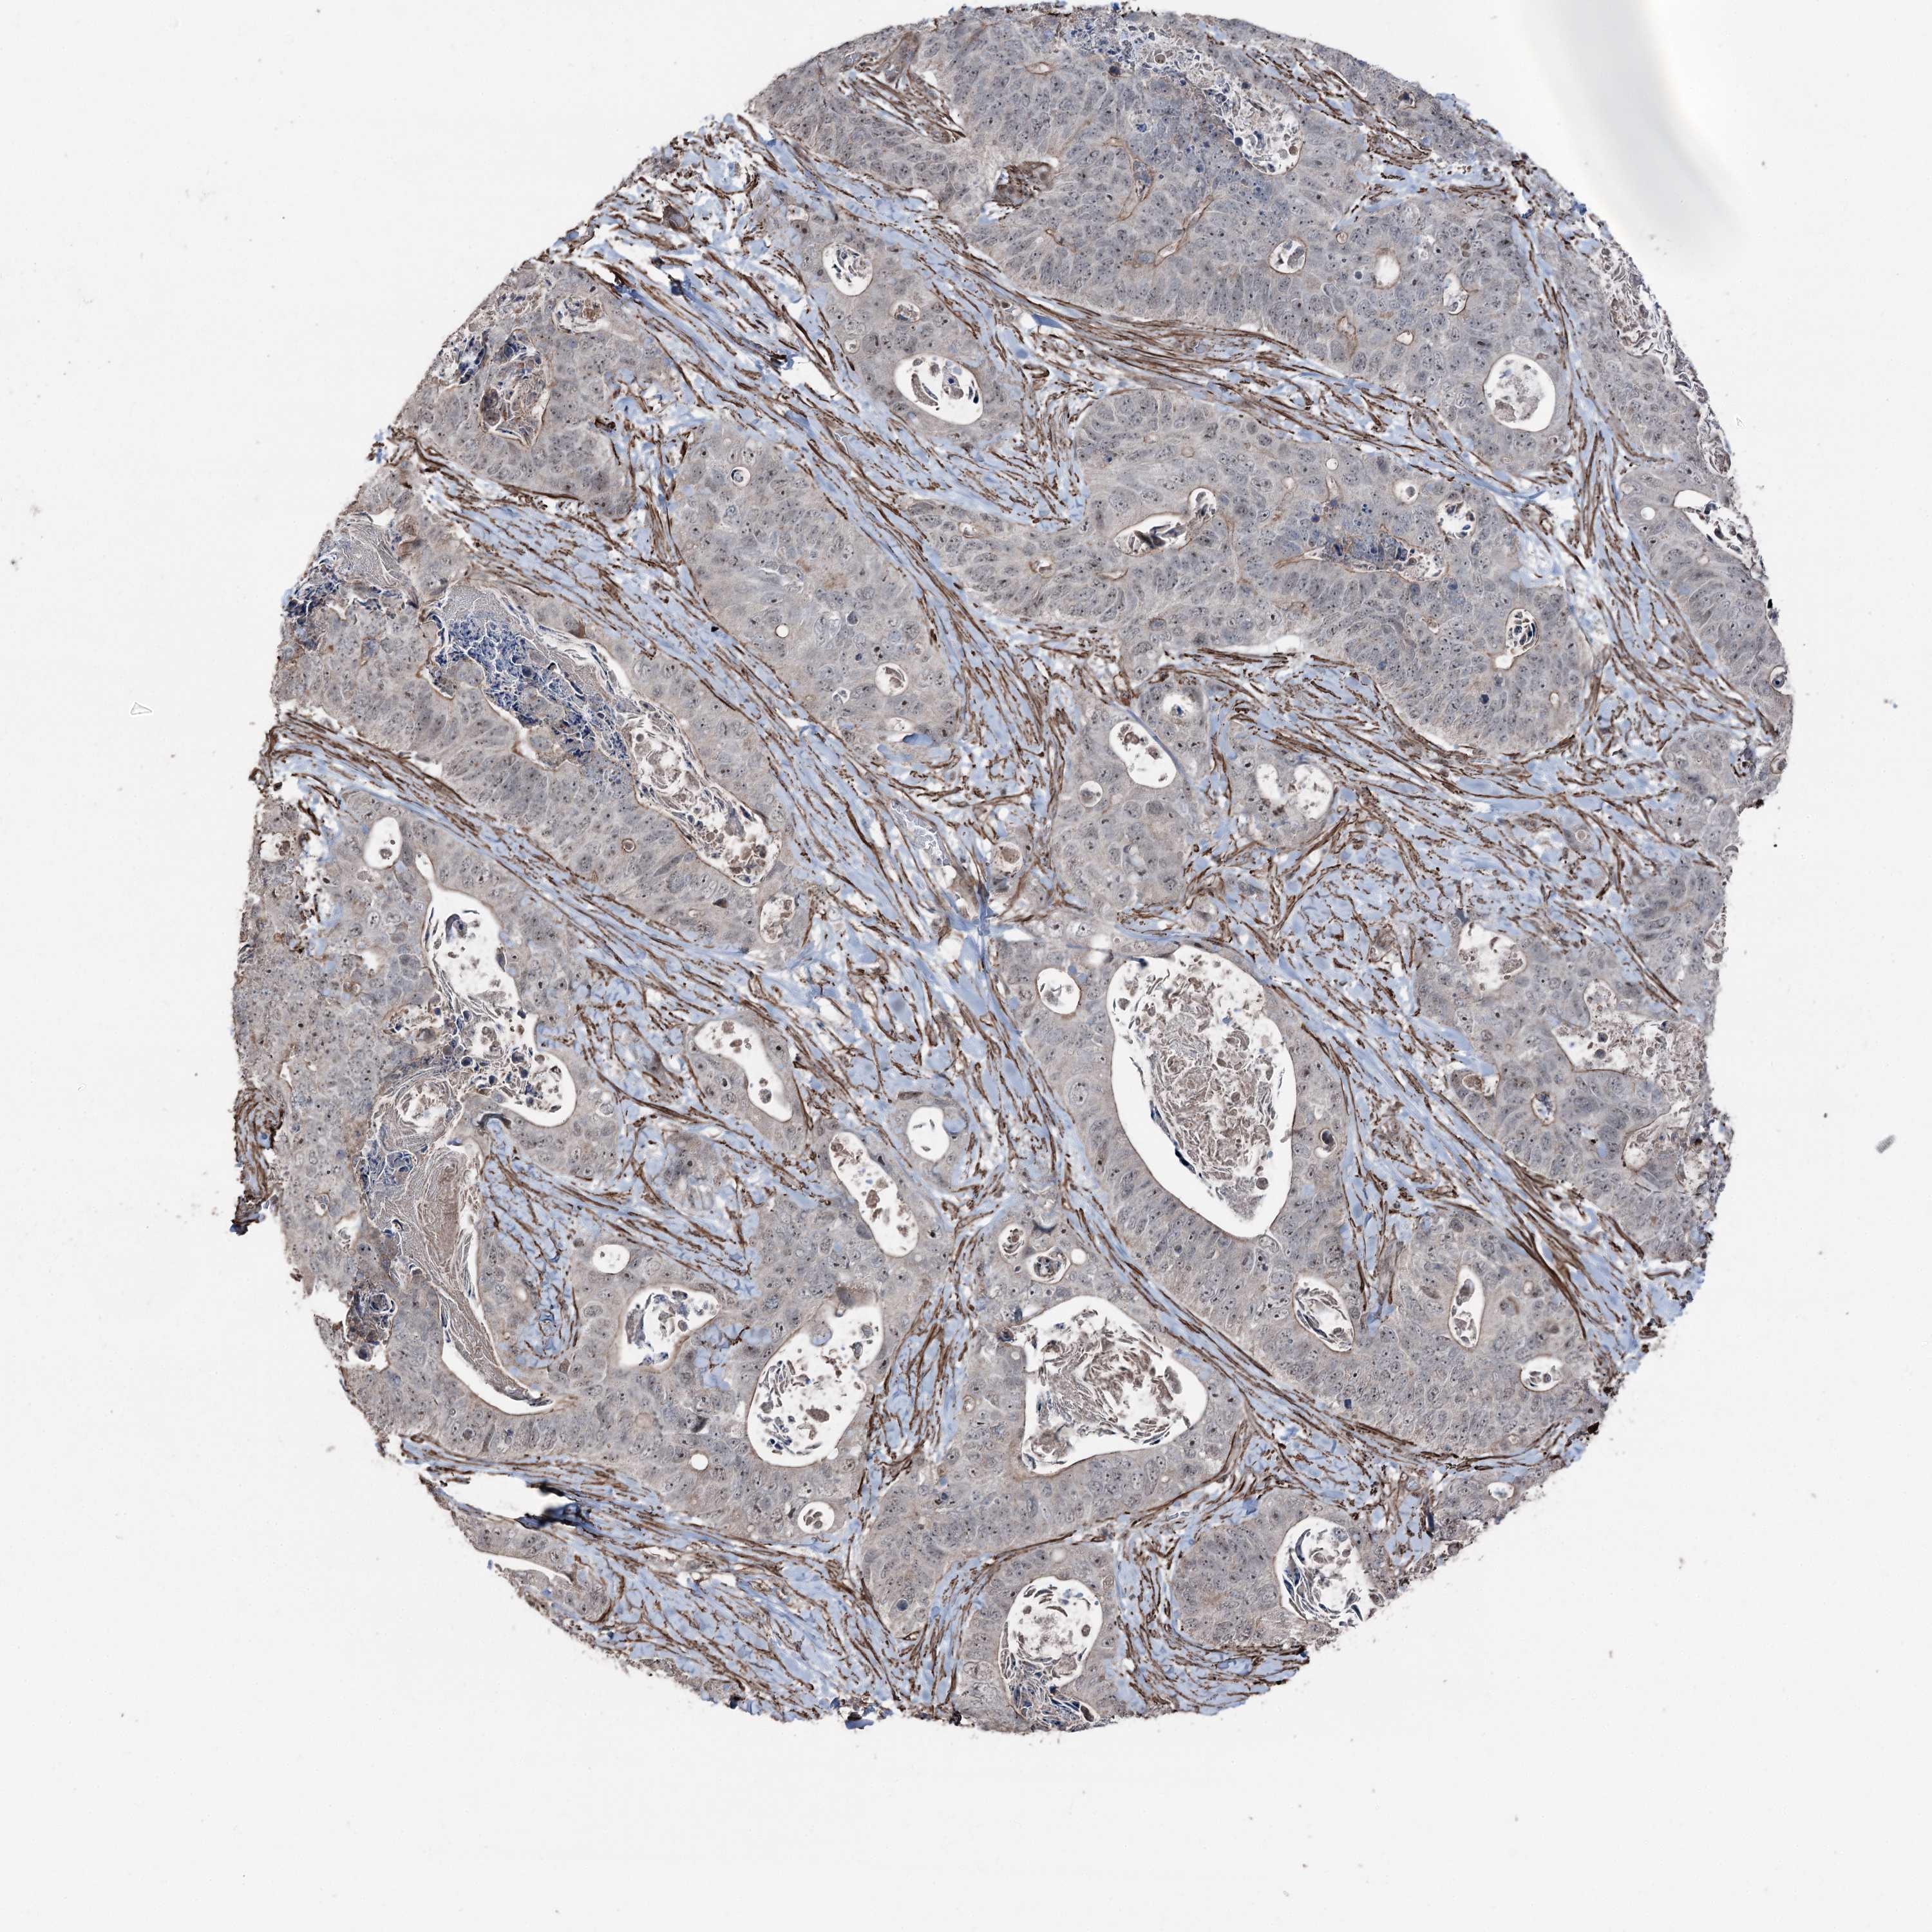

STOMACH CANCER - Protein expressioni

A mouse-over function shows sample information and annotation data. Click on an image to view it in a full screen mode. Samples can be filtered based on level of antibody staining by selecting one or several of the following categories: high, medium, low and not detected. The assay and annotation is described here.

Note that samples used for immunohistochemistry by the Human Protein Atlas do not correspond to samples in the TCGA dataset.

Antibody stainingi

Antibody staining in the annotated cell types in the current human tissue is reported as not detected, low, medium, or high, based on conventional immunohistochemistry profiling in selected tissues. This score is based on the combination of the staining intensity and fraction of stained cells.

Each image is clickable and will lead to virtual microscopy that enables deeper exploration of all samples and also displays staining intensity scores, fraction scores and subcellular localization as well as patient and tissue information for each sample.

Antibody HPA038704

Staining

High

Medium

Low

Not detected

Intensity

Strong

Moderate

Weak

Negative

Quantity

>75%

75%-25%

<25%

None

Location

Nuclear

Cytoplasmic/membranous

Cytoplasmic/membranous,nuclear

Adenocarcinoma, NOS